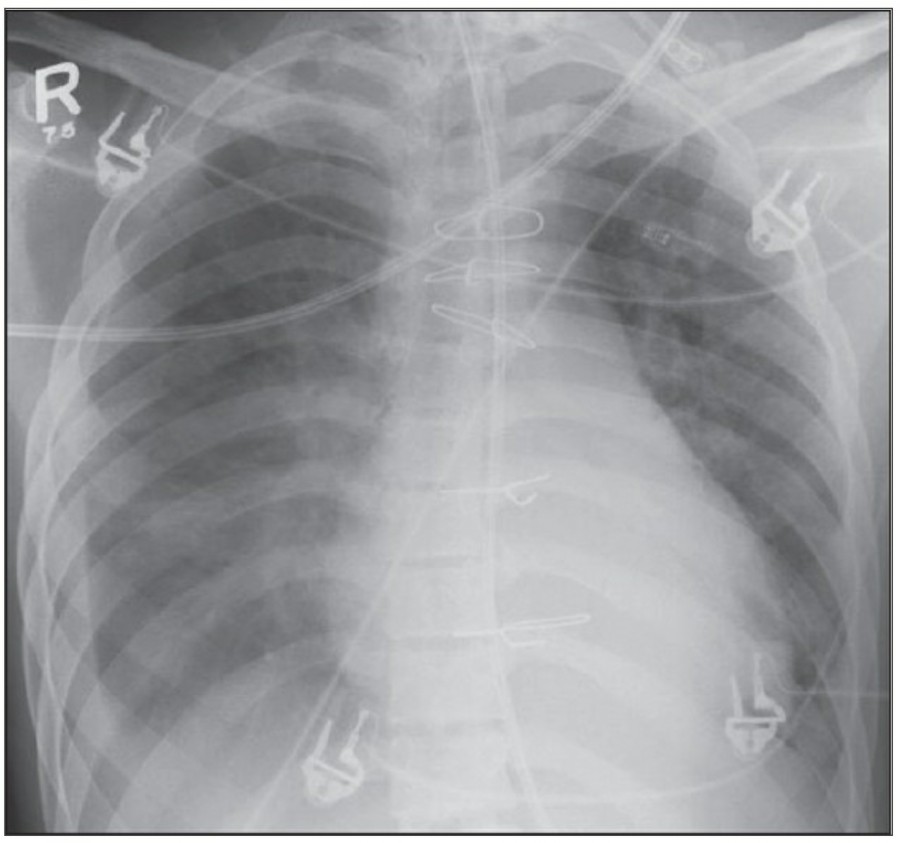

Central venous catheters

CVP tip의 이상적인 위치는 subclavian vein이나 jugular vein의 가장 proximal venous valve와 right atrium 사이다. CVP tip이 internal jugular vein이나 right atrium, right ventricle에 위치하는 경우는 드물지 않으며, superior vena cava보다 원위부에 위치하는 경우 arrhythmia나 cardiac perforation이 발생할 수 있다.

Monitoring pulmonary capillary wedge pressure Pulmonary

Swan-Ganz catheter의 tip은 mdiastinal shadow에 위치해야 하며, interlobar pulmonary artery의 근위부가 이상적이다.

Cardiac pacing devices

Temporary cardiac pacemaker는 cephalic vein이나 subclavian vien을 통해 right ventricl에 거치시킨다. AP, lateral chest X ray가 위치 확인을 위해 필요한다. Cardiac pacemaker의 tip은 심첨부에 위치해야 하며, pacemaker wire의 line이 꺾여 있어서는 안 된다. Lateral radiograph가 cardiac trabeculae 안에 묻혀 있는 tip을 확인하는데 도움이 된다. 제대로 거치된 게 맞다면 그 tip은 epicardial fat pad의 3, 4mm 안에 있어야 하며, 그 이상 넘어간다면 myocardium 천공 가능성이 있다. Coronary sinus 안에 들어갔을 경우 lateral radiograph 상에서 posterior 쪽에서 발견할 수 있다.